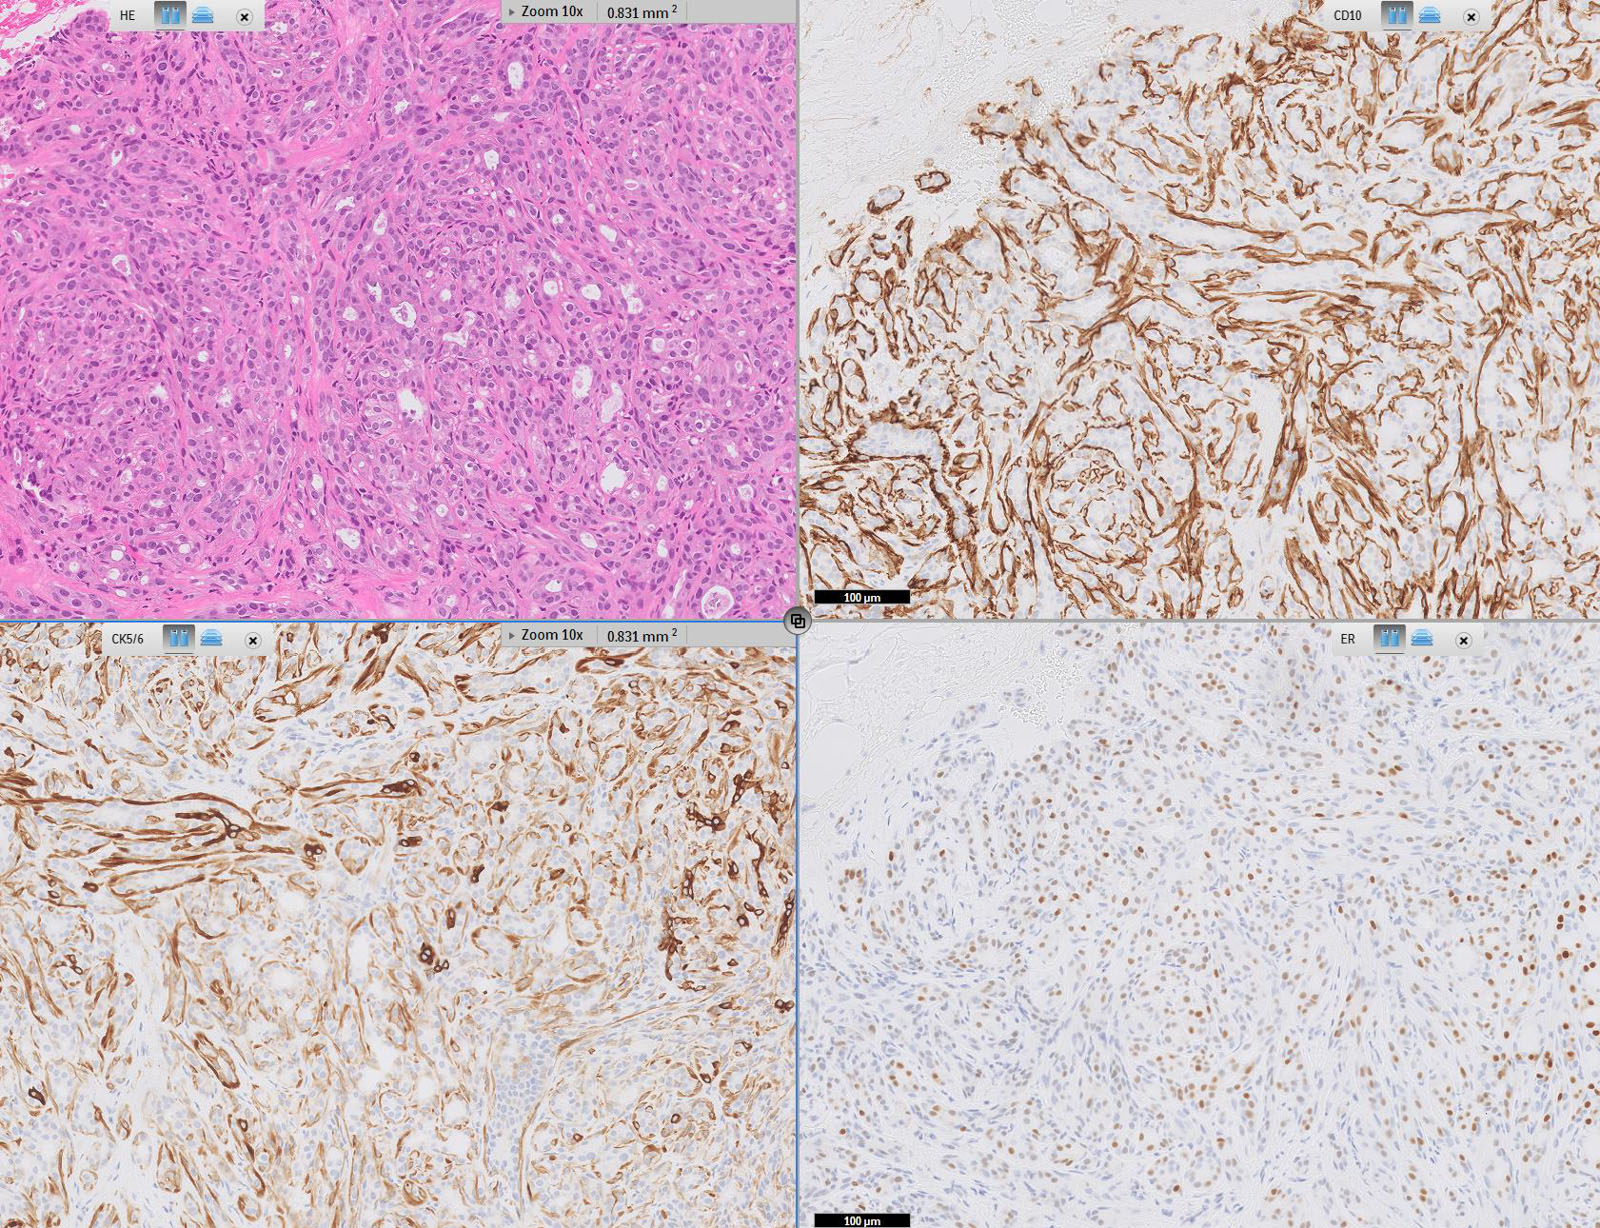

Microscopic (histologic) description

- Well defined borders

- Sparse fibrovascular stroma intervening tubules

- Small, uniform, closely packed round tubules (Clin Med Insights Pathol 2018;11:1179555718757499)

- Lined by an inner layer of luminal epithelial cells and an outer layer of myoepithelial cells

- Rare mild atypia and mitotic figures does not exclude diagnosis

- Occasional luminal eosinophilic secretion

- Lined by an inner layer of luminal epithelial cells and an outer layer of myoepithelial cells

Microscopic (histologic) images

Contributed by Joshua J.X. Li, M.B.Ch.B. and Gary M. Tse, M.B.B.S.

Positive stains

Negative stains